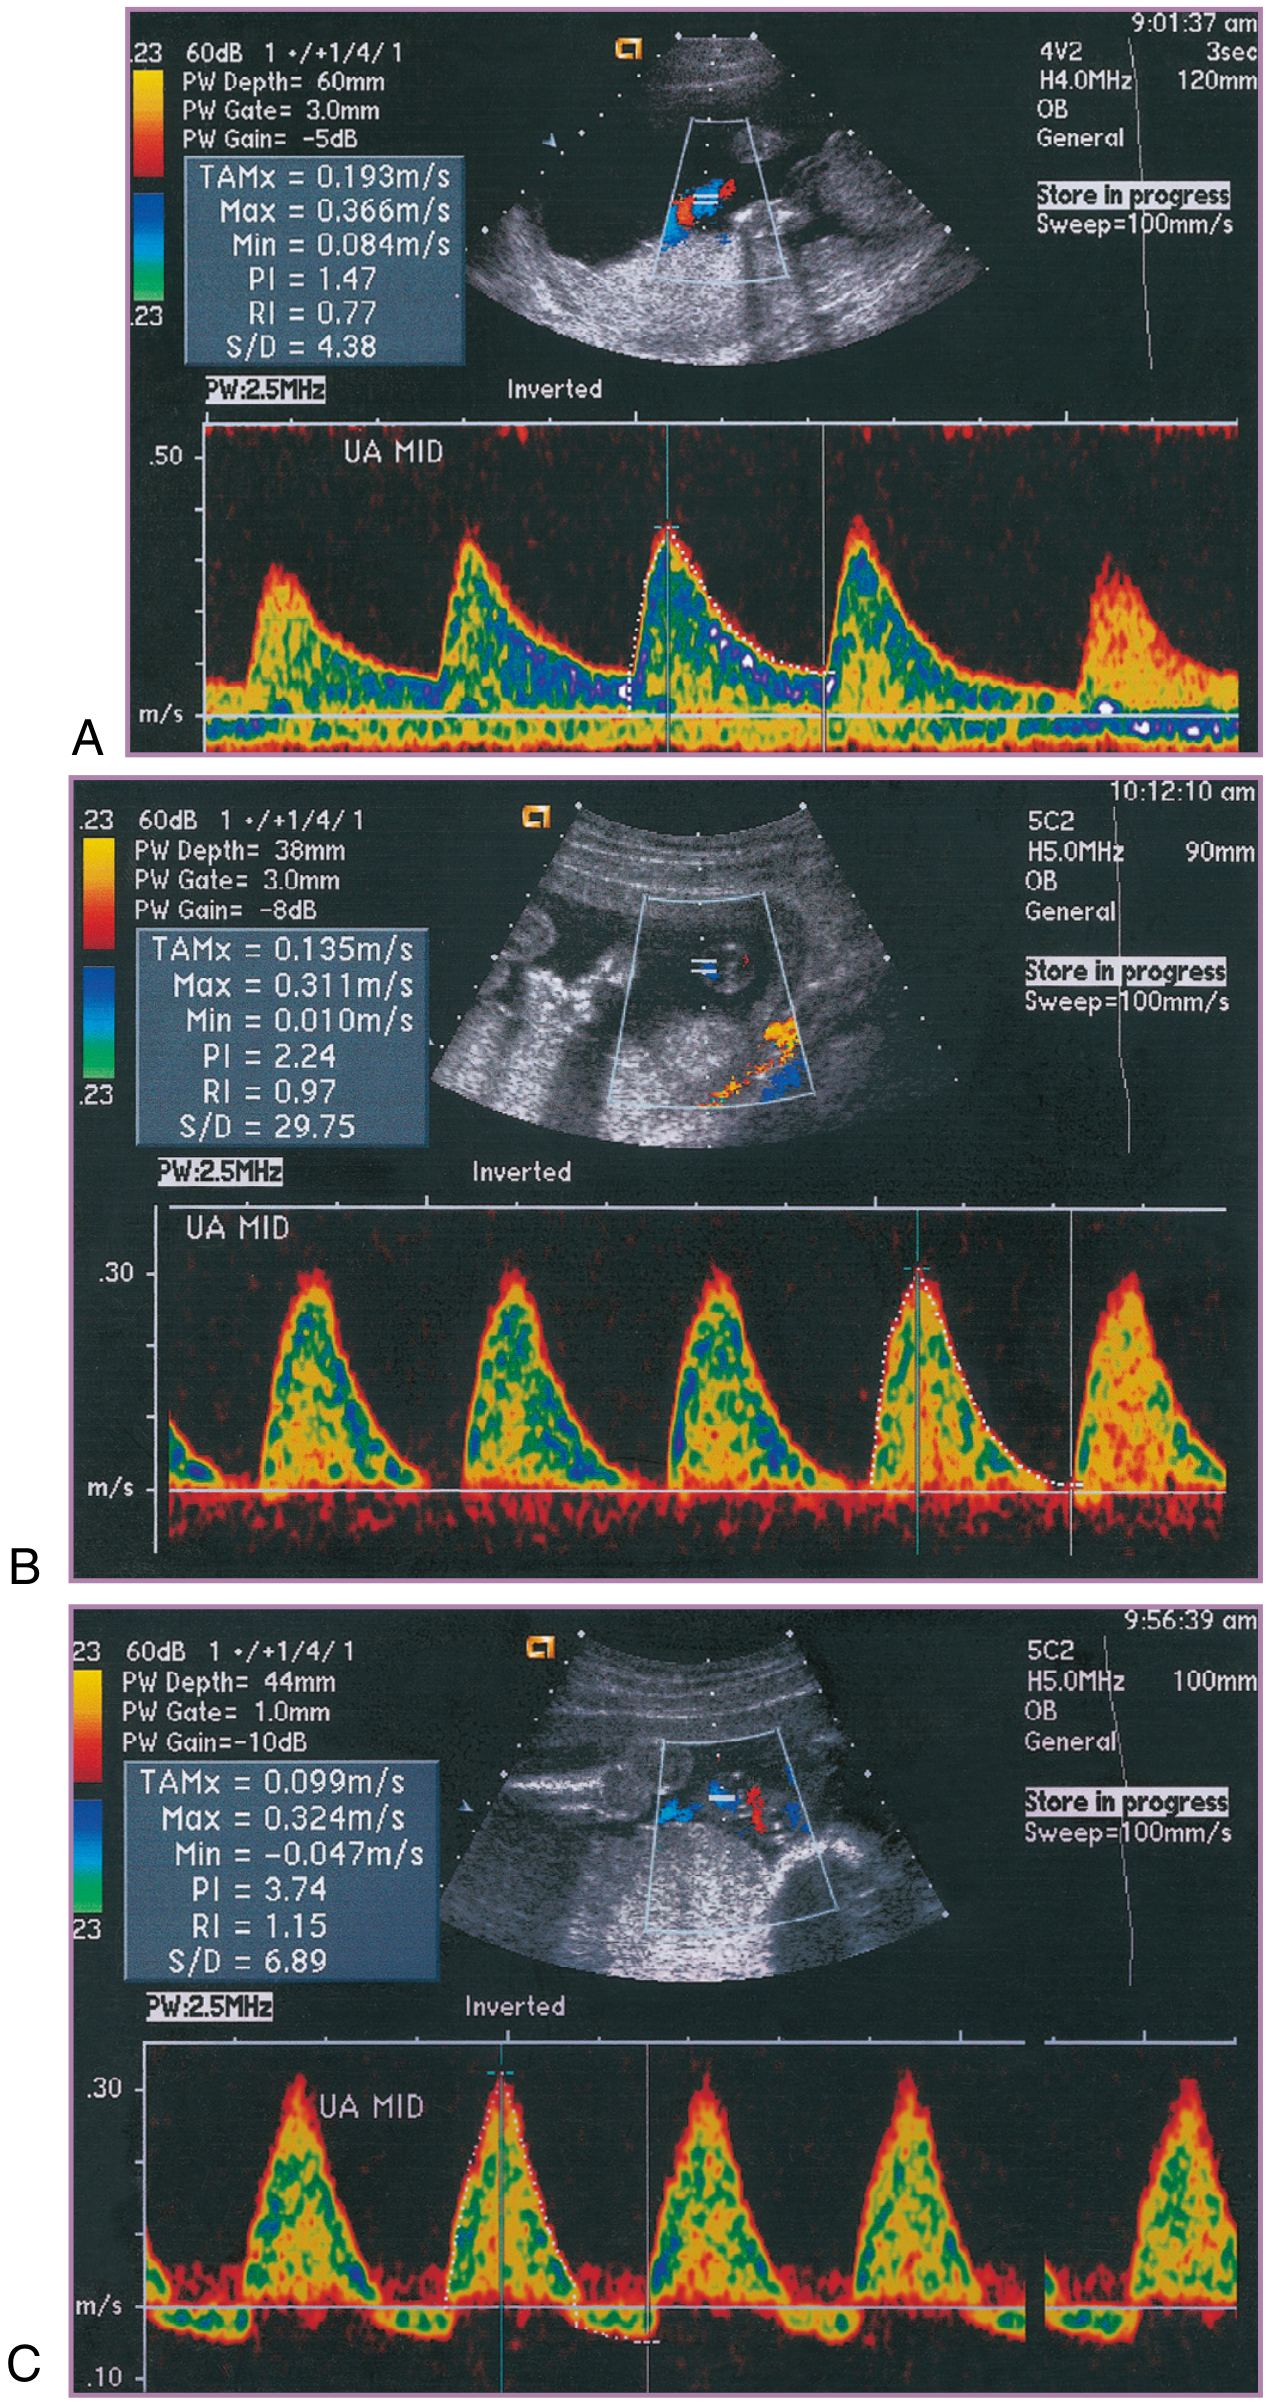

Umbilical Artery (UA) Doppler

• Reflects placental vascular resistance

• Normal: diastolic flow present and progressive throughout pregnancy

• Abnormal patterns (in order of severity):

1. Elevated S/D ratio / increased PI, RI — increased resistance

2. Absent End-Diastolic Velocity (AEDV) — critical worsening

3. Reversed End-Diastolic Velocity (REDV) — imminent fetal compromise; strong indicator for delivery

Umbilical artery Doppler waveforms

Figure: Progressive umbilical artery resistance — from nearly normal at 18 weeks to absent end-diastolic velocities at 24 weeks